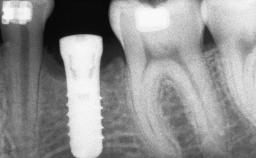

# of Implants 14

Type of Implants Two-Piece

Bone Augmentation Horizontal|Sinus Floor Elevation|Staged|Vertical

Bone Volume Deficient vertically or deficient vertically AND horizontally